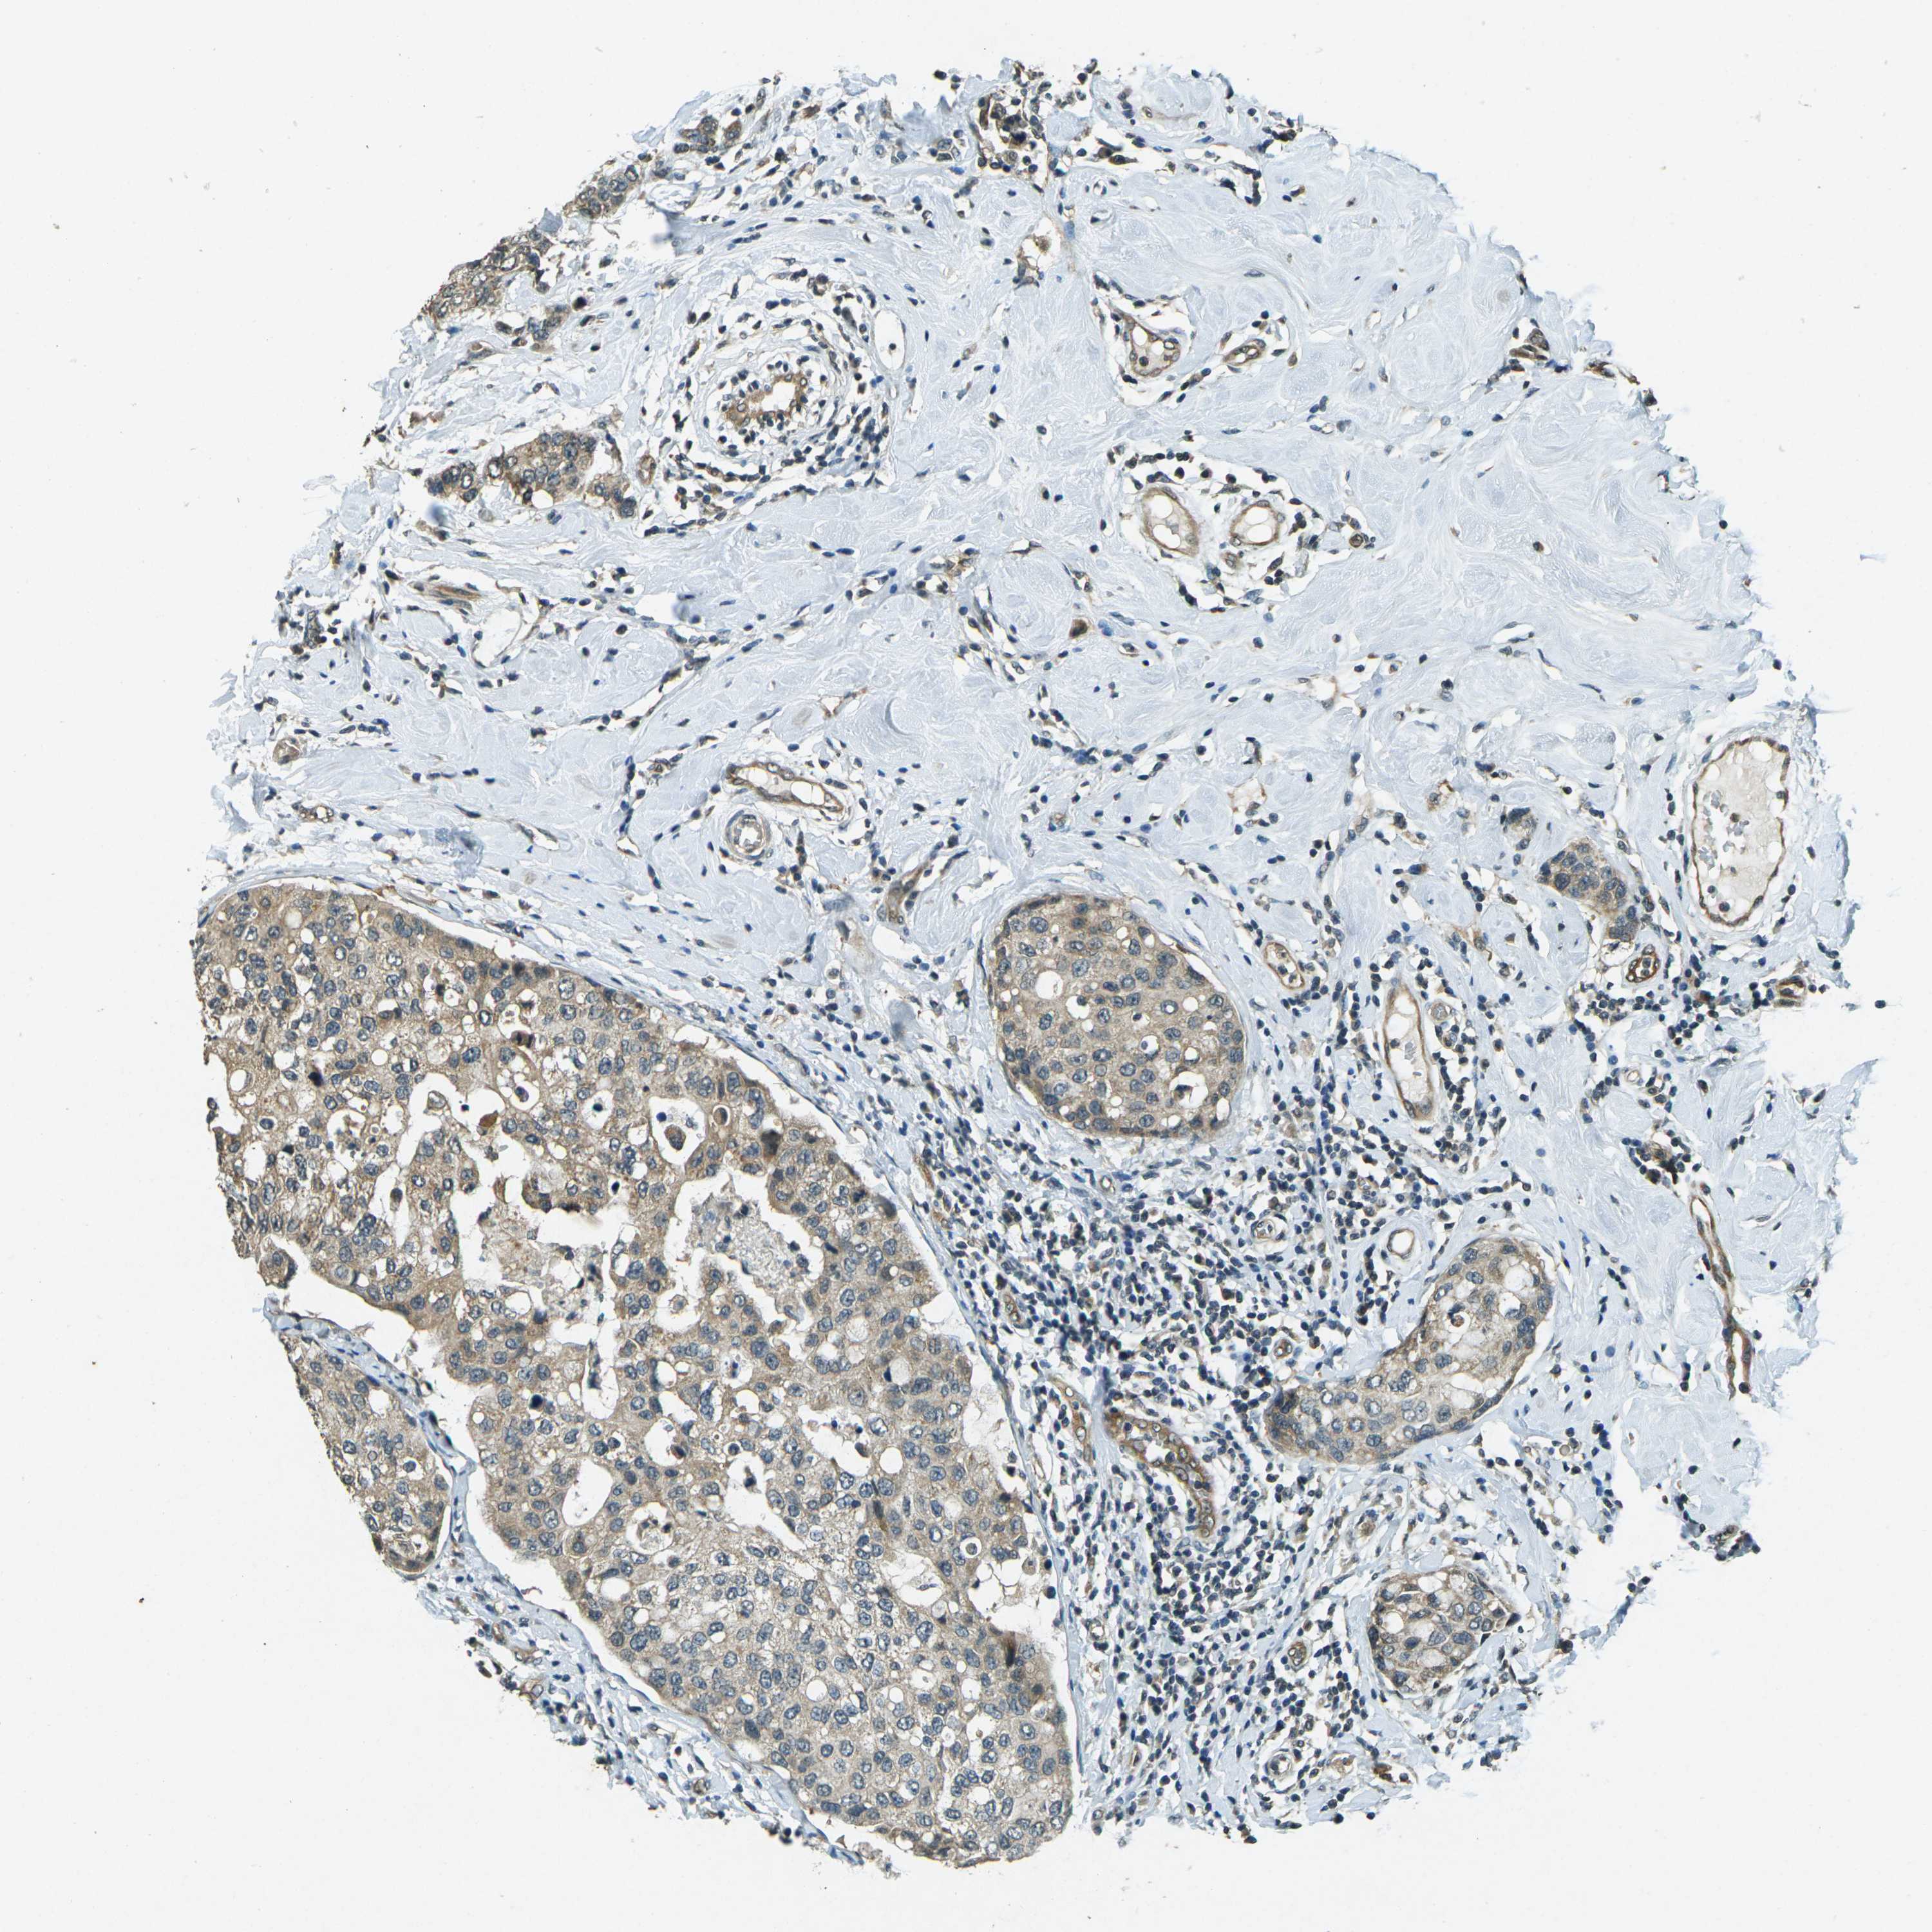

CANCER BREAST CANCER Show tissue menu

BRCA TCGA BRCA VALIDATION PROTEIN EXPRESSION

ANTIBODIES

AND

VALIDATION